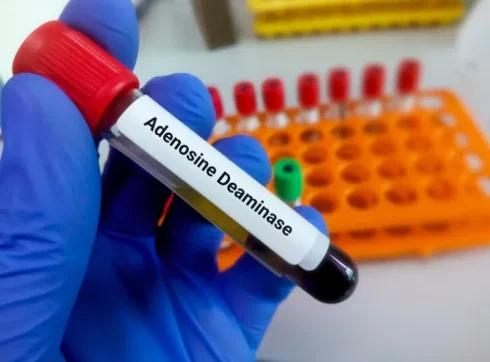

آزمایش آدنوزین دآمیناز (ADA) چیست؟ تفسیر نتایج آزمایش ADA

خلاصه آزمایش آدنوزین دآمیناز (ADA) با جمعآوری نمونهای از مایع پلور در محیطهای بالینی انجام[بیشتر بخوانید]